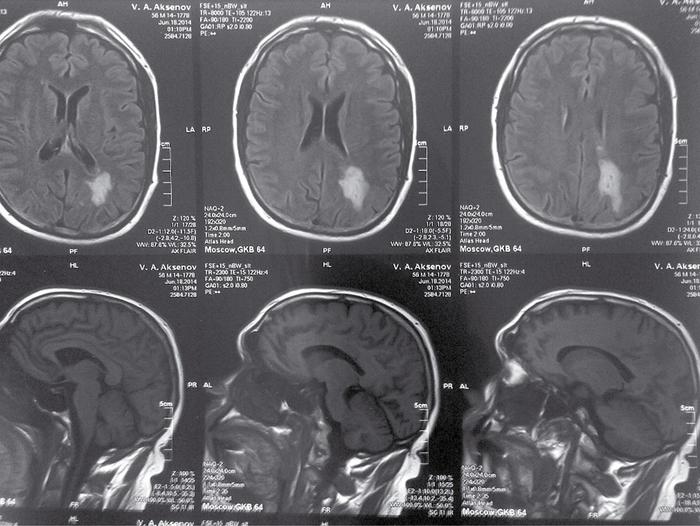

При неврологическом обследовании в момент обращения не было выявлено явных очаговых симптомов. Нейровестибулярное исследование показало отсутствие спонтанного и позиционного нистагма. МРТ выявила изменения, соответствующие недавно перенесенному ишемическому инсульту в области теменно-затылочных районов левого полушария.

Необъяснимое головокружение требует выполнения МРТ даже при отсутствии других очаговых неврологических симптомов. Изменения, выявленные на МРТ, могут указывать на ишемический инсульт.